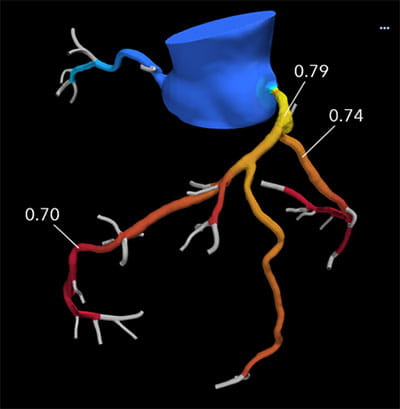

• High volume program with daily case averages of 10 CMR studies and 25-35 cardiac CTAs (50% coronary CTA, 30% structural, 20% other). Broad case complexity, including CAD, structural heart pathologies, congenital heart disease,  and implantable devices. Routine use of cutting edge technology, including T1/ECV mapping, quantitative perfusion, free-breathing CMR exam, artificial intelligence based CT analyses, CT-FFR, structural planning and simulation.